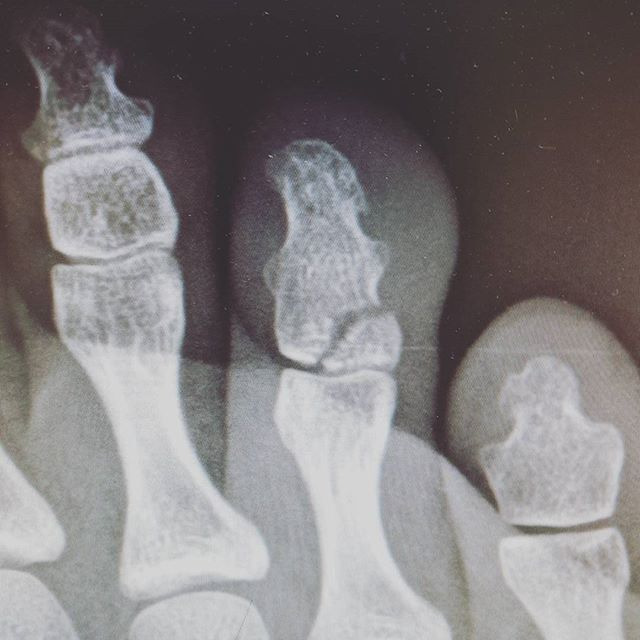

발가락 골절 완치기간 (엄지발가락, 새끼발가락)

발가락 골절은 위치에 따라 회복 과정과 치료 강도가 달라집니다. 발가락은 체중을 지탱하고 보행 시 반복적인 압력을 받기 때문에, 같은 골절이라도 손가락보다 회복이 느리게 진행되는 경향이 있습니다. 특히 엄지발가락은 보행 시 추진력을 담당하는 핵심 구조로, 단순 골절과 복합 골절의 구분이 중요합니다.

- 새끼발가락 및 2-5번째 발가락 단순 골절: 약 4-6주

- 전위(뼈가 어긋난 상태)를 동반한 골절 또는 관절 침범 골절: 8주 이상